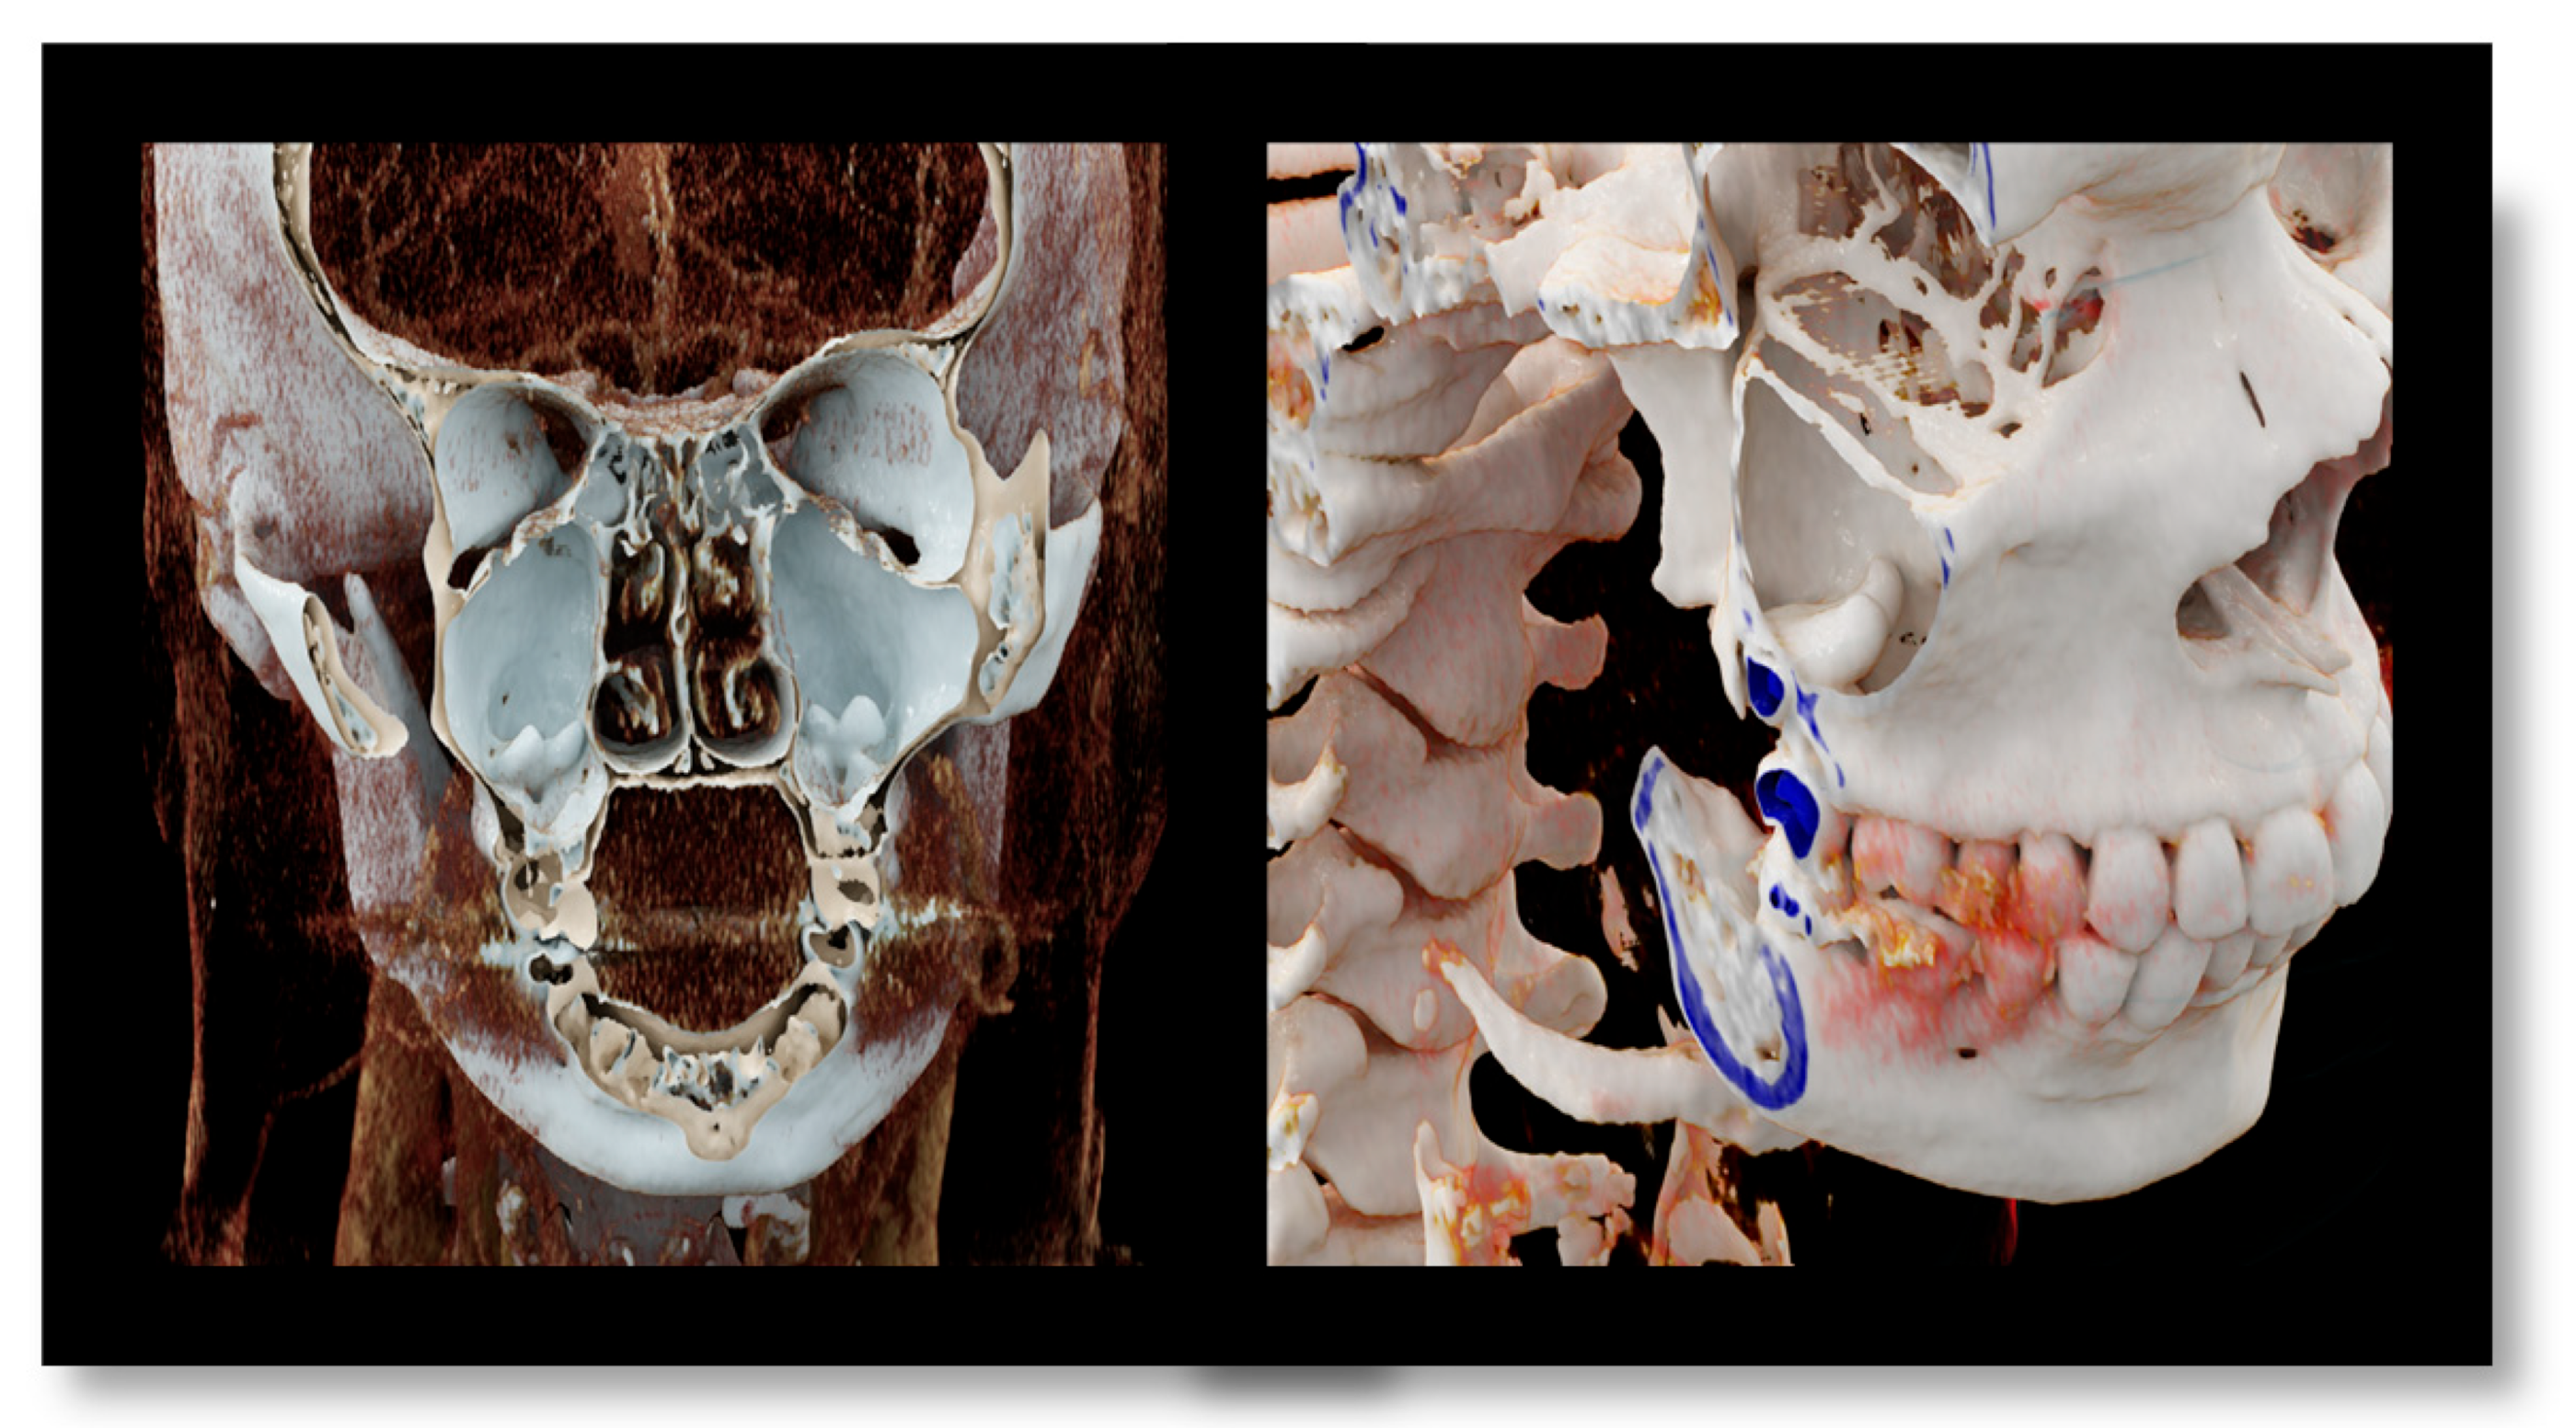

None of the reported works and cases have ever used volume rendering (VR) or CR for three-dimensional visualization of the molar in the maxillary cavity.

CT provides detailed information about the location and morphology of the ectopic tooth, as well as the evaluation of surrounding anatomical structures, facilitating treatment planning.

In the present case, CT was used to visualize the ectopic teeth in the maxillary sinus. CT has been widely used to diagnose ectopic teeth in the maxillary sinus because it can provide detailed information about the location and morphology of the ectopic tooth. In addition, CT allows evaluation of the surrounding anatomical structures, such as the sinus walls and adjacent teeth, in light of a possible surgical treatment, facilitating its planning [

We also used cinematic rendering to visualize the ectopic teeth in the maxillary sinus. By simulating the propagation and interaction of light beams as they move through the volumetric data, cinematic rendering creates a representation of 3D pictures that is more lifelike than that produced by ordinary volume rendering [

11]. In general, cinematic rendering uses the same procedures as volume rendering to determine color and opacity: transfer functions are employed to convert the gray values in each voxel of the original pictures to a color and opacity value. Afterward, a variety of transfer functions can be used for rendering, based on the case’s features and the structures that should be highlighted. However, the algorithm used in cinematic rendering is based on path-tracing techniques and the global illumination model, which simulate the various paths that billions of photons traveling from all possible directions take through a volumetric dataset and their interaction with the volume to form one pixel. This is in contrast to ray casting techniques, in which each pixel is formed by one light ray. As a result, this recently introduced 3D reconstruction technique provides more realistic 3D images with high spatial resolution and excellent tissue differentiation. Just like VR, CR can offer insights into various tissue types by adjusting the display parameters to enhance the visualization of soft tissues compared to denser structures. CR’s shadowing capabilities can enhance our understanding of anatomy, especially in areas with complex structures, including those with overlapping or protruding elements. However, it is worth noting that the prospective view in CR may partially obscure deeper regions.

In contrast to traditional VR, which treats each reconstructed voxel independently, CR presents neighboring voxels interactively. This adaptability allows for the manipulation of lighting and shadow conditions in a panoramic view. Furthermore, in addition to shadowing, CR’s global lighting model excels at revealing intricate anatomical details, making it particularly useful for visualizing small structures [

Overall, the use of CT and film rendering in our case allowed us to accurately diagnose and localize the ectopic teeth in the maxillary sinus. These imaging modalities are valuable tools in the diagnosis and management of ectopic teeth in the maxillary sinus and may aid in the planning of surgical interventions [